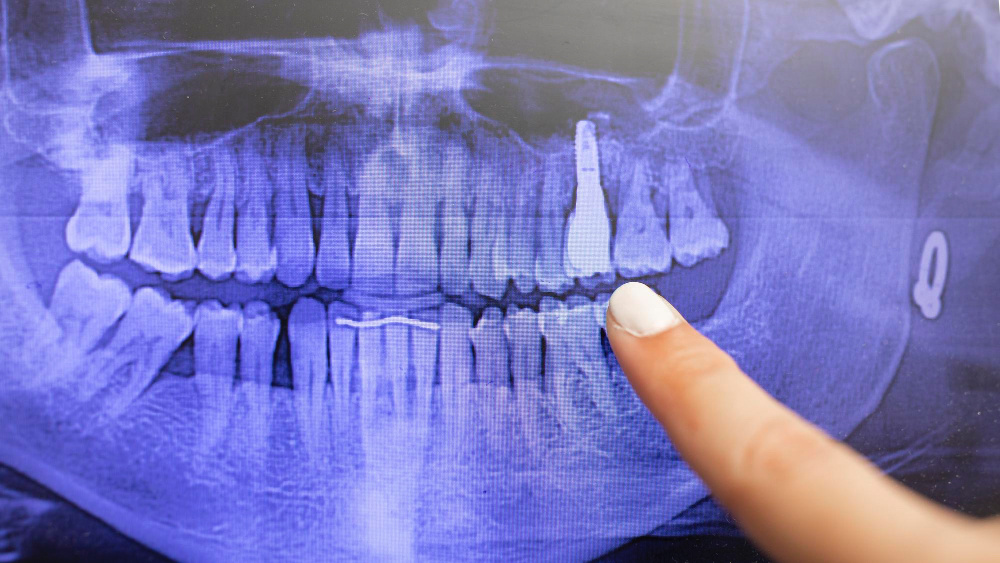

Компьютерная томография (КТ) зубов и челюсти — это современный метод диагностики, который активно применяется в стоматологии. Он позволяет получить трёхмерное изображение зубов, костной ткани и окружающих структур, что важно для точного планирования лечения. Однако у многих пациентов возникает вопрос: опасно ли делать КТ из-за радиационного воздействия?

Да, при проведении КТ используется рентгеновское излучение, которое действительно связано с воздействием радиации. Однако современные аппараты для дентальной компьютерной томографии разработаны таким образом, чтобы минимизировать дозу облучения. В стоматологии применяются низкодозовые КТ-сканеры, которые обеспечивают высокую детализацию изображения при минимальном уровне радиации. Например, доза облучения при КТ челюсти значительно ниже, чем при стандартной компьютерной томографии всего тела или даже при некоторых медицинских рентгенологических исследованиях.

Для сравнения, доза радиации при одном сеансе дентальной КТ эквивалентна дозе, которую человек получает за несколько дней естественного фонового облучения (например, от солнечной активности или радиоактивных элементов в окружающей среде). Это делает процедуру безопасной при соблюдении всех стандартов и рекомендаций.

Важно отметить, что назначение КТ проводится только по показаниям врача. Процедура необходима в сложных случаях, например, при планировании имплантации, лечении кисты, удалении зубов мудрости или диагностике заболеваний челюстных суставов. Если врач считает КТ необходимым, польза от точной диагностики значительно превышает потенциальные риски.